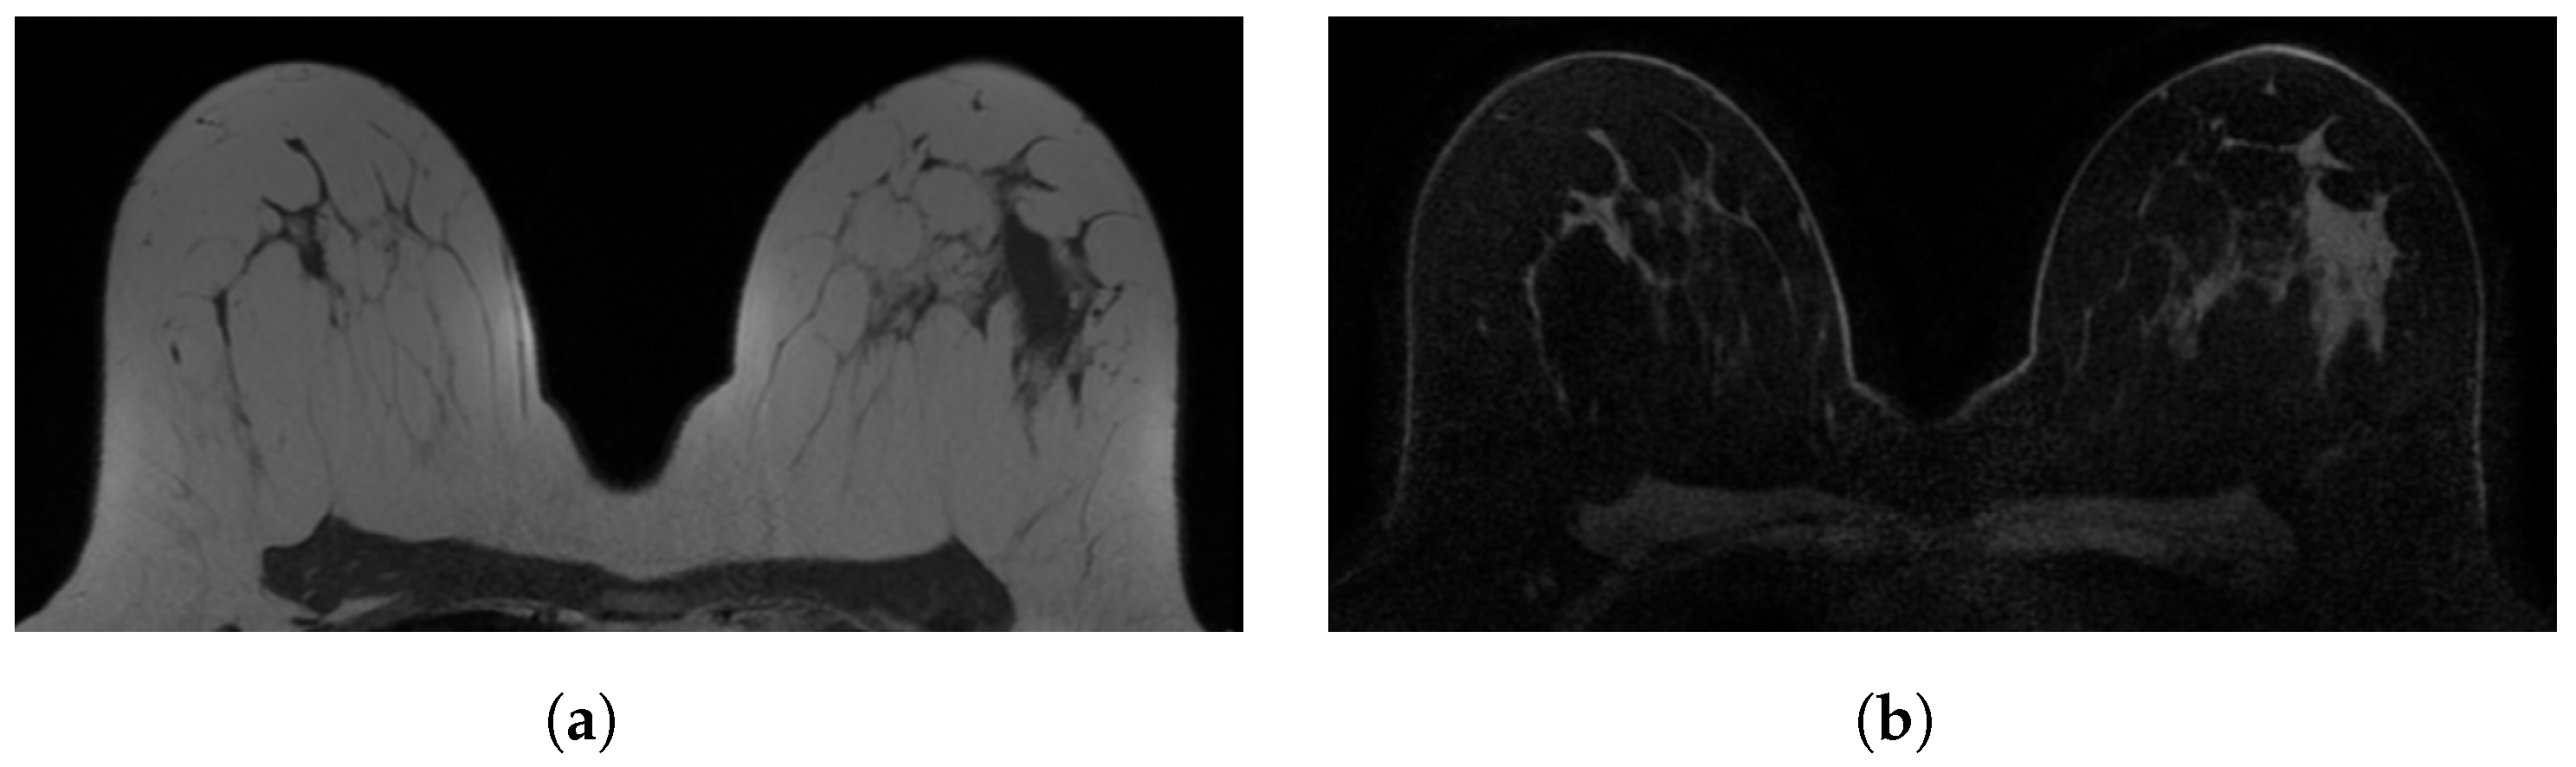

Figure 1. Examples of in-phase and reconstructed water Dixon acquisitions from our internal dataset used to mimic acquisitions without (WOFS) and with (FS) fat suppression. (a) In-phase Dixon acquisition used as WOFS image. (b) Reconstructed water Dixon acquisition used as FS image.

2. Materials and Methods

In this retrospective study, 40 patients were selected from the PACS system of our institution (Radbodumc, Nijmegen, The Netherlands) based on the availability of breast DCE-MRI acquisitions acquired with the use of the Dixon method. All the scans were acquired between November 2015 and February 2017. Patients (mean age 50 ± 21 years, all females) were all participating in an increased-risk breast cancer screening program that consisted of annual MRI with or without concurrent mammography, with no previous history of breast cancer. All breast MRI acquisitions were obtained using a 3T breast MRI scanner (Siemens Trio, Prisma or Skyra) and at least a 16-channel breast coil. Breast MRI acquisition protocols have slightly changed over time, but all met the minimal standards described within the EUSOBI breast MRI guideline. Table 1 shows an overview of the acquisition parameters. All the acquisitions included in this study were pre-contrast T1-weighted 3D Dixon-type acquisitions. Only the in-phase and the reconstructed water acquisitions were used from the four available (in-phase, out-of-phase, reconstructed water and fat) Dixon outputs. The in-phase and the reconstructed water acquisitions, respectively, are WOFS (Figure 1a) and FS (Figure 1b) acquisitions. We divided the dataset into training (n = 31 patients, 62 acquisitions (31 WOFS, 31 FS) and testing (n = 9 patients, 18 acquisitions (9 WOFS, 9 FS)). The testing set was held out completely from the implementation of the segmentation network and it was used only for the final validation.